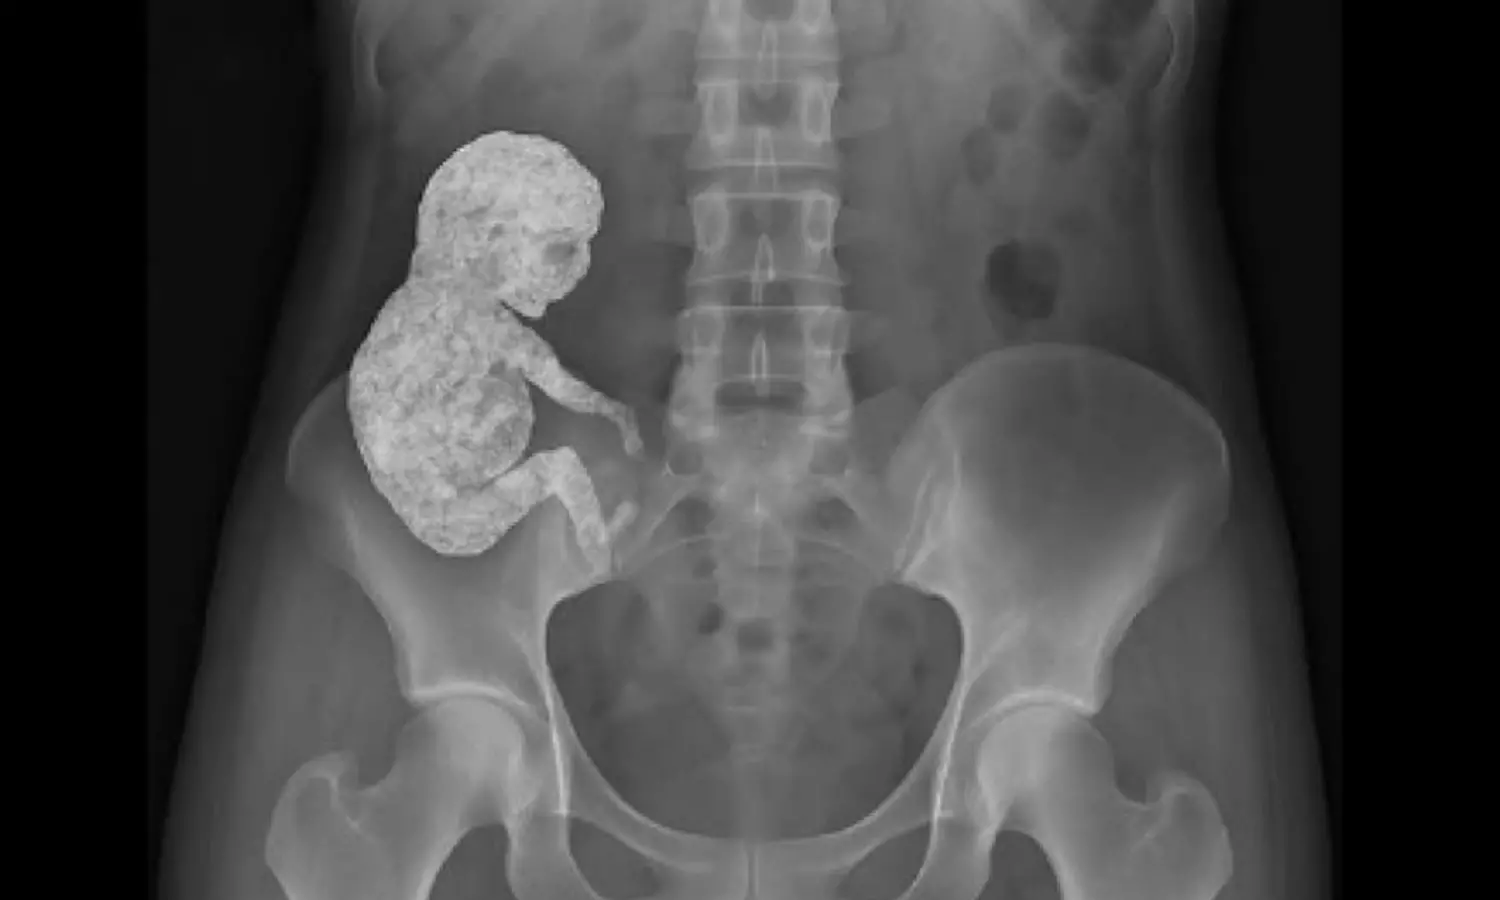

కారణం ఆమె శరీరంలో 40 సంవత్సరాలకు పైగా ఒక కాల్సిఫైడ్ గర్భస్థ శిశువు ఉంది. అంటే 40 సంవత్సరాలుగా ఆమె గర్భవతి అన్నమాట. ఈ అరుదైన పరిస్థితిని వైద్య పరిభాషలో లిథోపెడియన్ లేదా స్టోన్ బేబీ అని పిలుస్తారు. అంటే గత 40 ఏళ్ల క్రితం ఆ మహిళకు ఎక్టోపిక్ గర్భం ఏర్పడిందట . అంటే గర్భస్థ శిశువు గర్భం లోపల కాకుండా గర్భం బయట అభివృద్ధి చెందడం.. దీని కారణంగానే ఆ మహిళకు పురిటి నొప్పులు అందరి లాగే రావడం , బిడ్డను కనడం వంటి పరిస్థితి ఎదురు కాలేదు.

పైగా ఈ సంక్రమణను నిరోధించడానికి అనుగుణంగా ఆమె శరీరం గర్భస్త శిశువును క్యాల్షియంతో ఆవరించి ఒక రక్షణ కవచాన్ని ఏర్పాటు చేసిందట. ఫలితంగా శిశువు గర్భాశయం వెలుపలి భాగంలో ఒక మమ్మీ సైడ్ రూపంగా మారి నిశ్శబ్దంగా ఉండిపోయింది. అందుకే ఎటువంటి గర్భస్థ లక్షణాలను కూడా కనబరచలేకపోయింది. నిజానికి ఇలాంటి సంఘటనలు చాలా అరుదుగా మాత్రమే జరుగుతాయట. వైద్య చరిత్రలో ఇప్పటివరకు కేవలం 300 కేసులు మాత్రమే గుర్తించినట్లు వైద్యులు తెలిపారు. ఇకపోతే ఈ విషయం ఎక్కడ? ఎప్పుడు? ఎవరిలో జరిగింది అనే పూర్తి వివరాలు మాత్రం లేవు. కానీ సోషల్ మీడియాలో మాత్రం ఈ వార్త వైరల్ అవ్వడంతో అందరూ ఆశ్చర్యపోతున్నారు. ఏది ఏమైనా ఇలాంటి సంఘటనలు అందరినీ ఆశ్చర్యానికి గురి చేస్తున్నాయి.